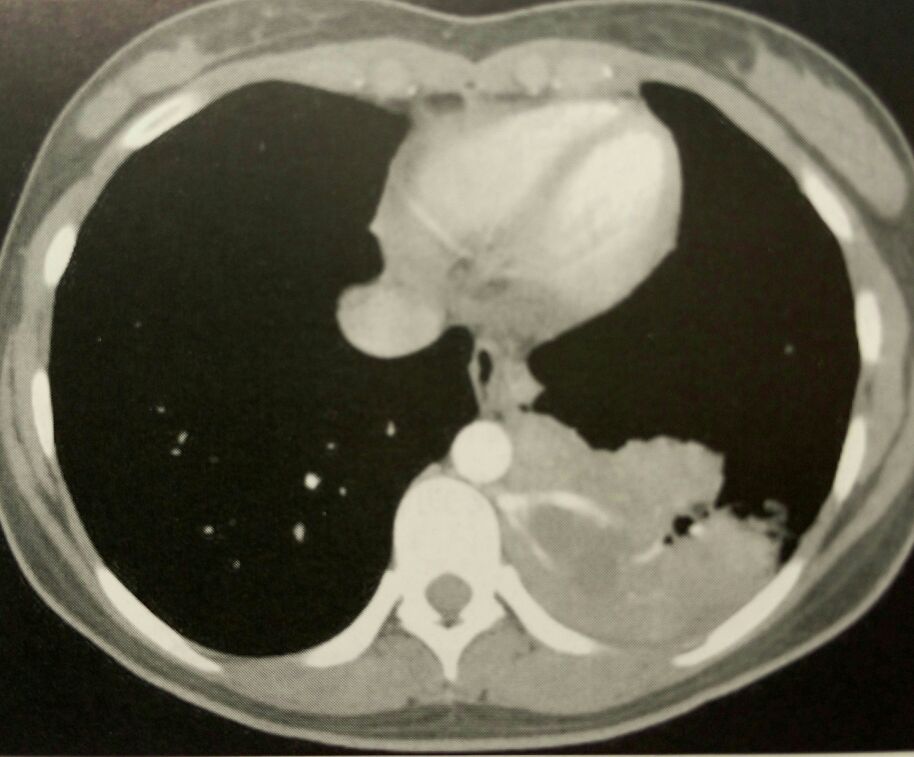

辅助检查胸部CT显示:右肺下叶近脊柱旁占位,考虑肺隔离症,合并感染可能。